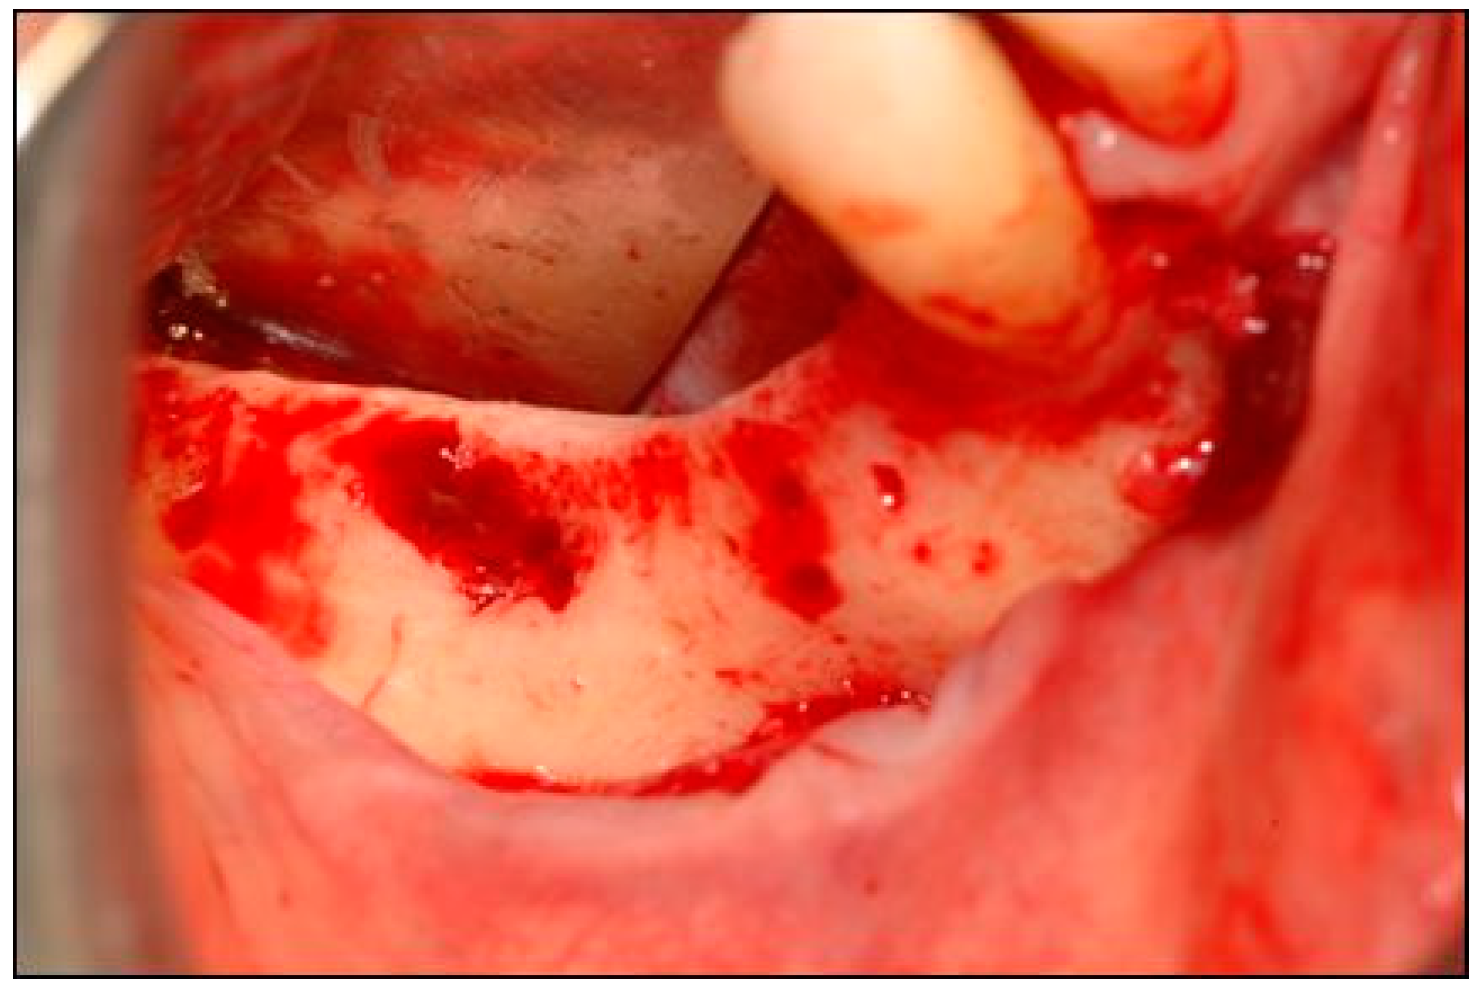

A Preshaped Titanium Mesh for Guided Bone Regeneration with an Equine-Derived Bone Graft in a Posterior Mandibular Bone Defect: A Case Report

2. Case Description